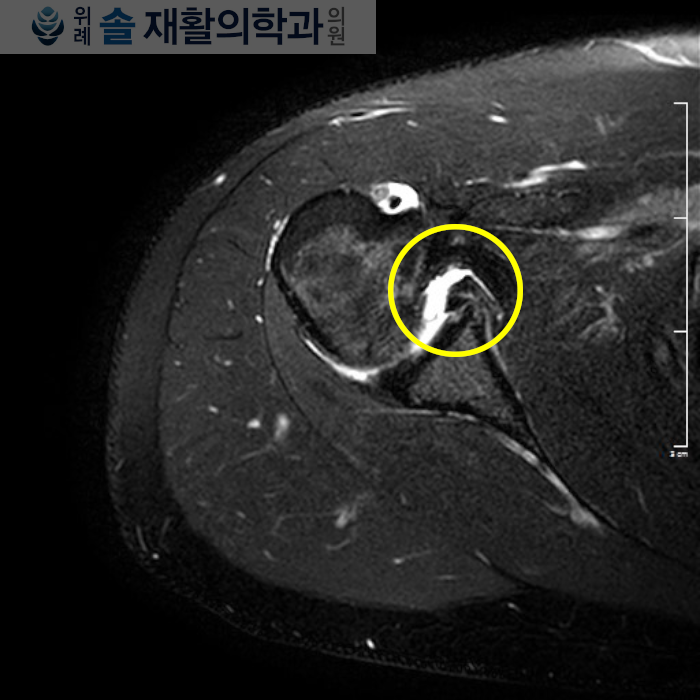

내원 당시 이미 본인의 진단명을 알고있는 상태로 내원하였고, 진단명은 #방카르트병변 이였습니다.

이 진단은 지참해 온 타병원 MRI 검사 소견을 보고 다시 확인하였습니다,

방카르트 병변(Bankart lesion)은 어깨의 외상성 운동 손상 중 가장 흔한 어깨 관절의 전방 탈구(#어깨빠짐)에 의해 유발되는데, 어깨 관절이 빠지면서 관절면에 부착되어있던 관절외순이라는 섬유조직이 뜯어져나가는 손상을 말합니다.

심한 손상의 경우에는 뼈도 같이 물고 떨어지는 경우가 있는데 이를 골성 방카르트 병변(Bony Bankart lesion) 이라고도 부릅니다.